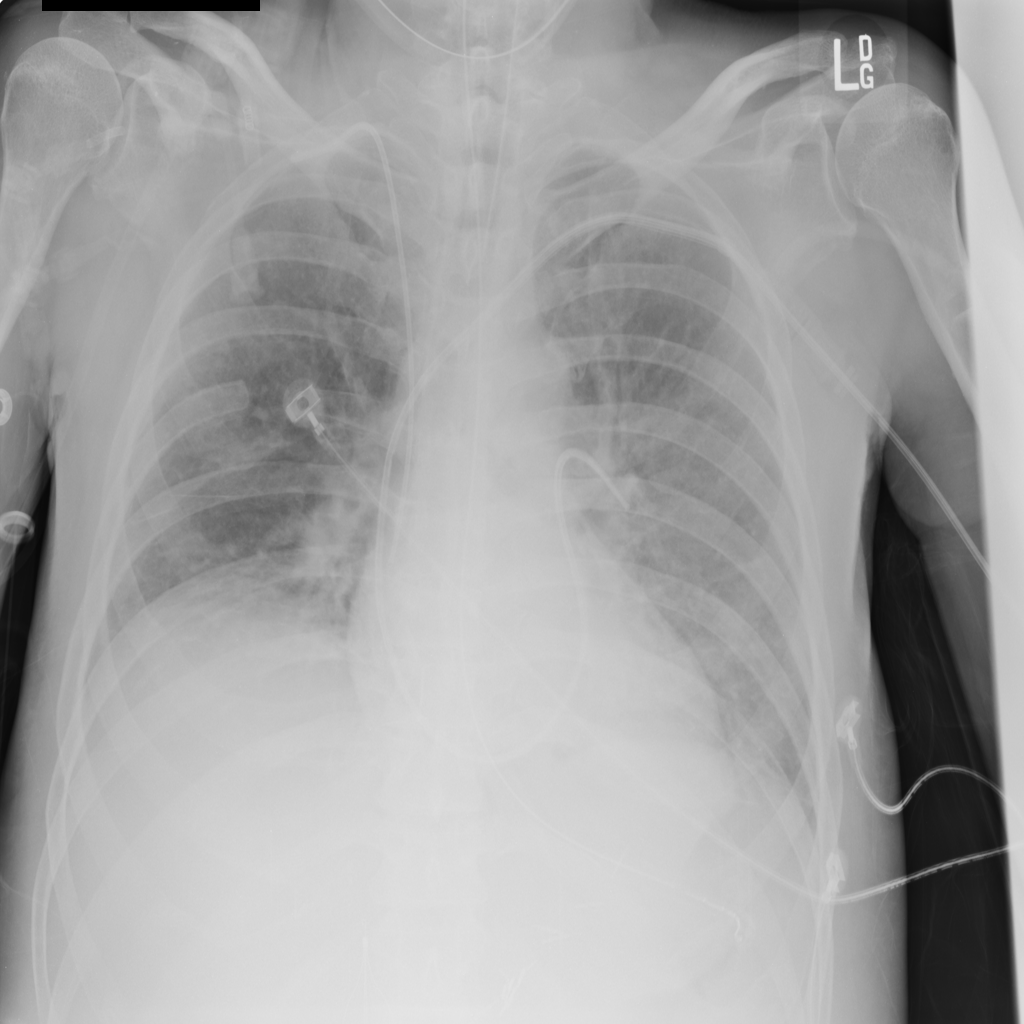

PAT-988D · IMG-001Nodule

PAT-988D · IMG-001

AP